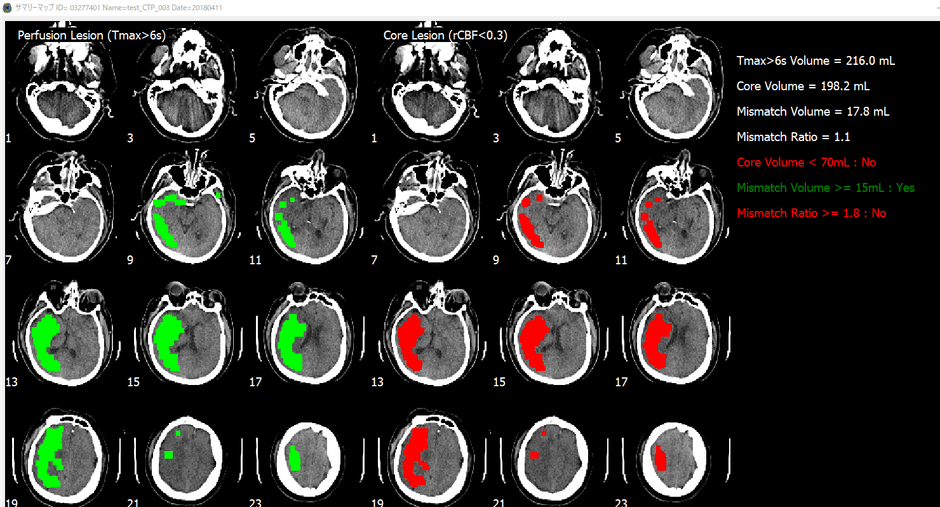

脳画像解析プログラム PMAneo(以下 PMAneo)は、MRI拡散強調画像から低ADC値領域を計測、またMRIまたはCT灌流画像からCBF、CBV、最大遅延時間を計測し、脳血流低下領域の容積およびこれらの差と比を算出、表示する、全自動脳画像解析ソフトウェアです。

PMAneoは、虚血コアと低灌流領域に相当する体積及びミスマッチの自動解析を数分で行う脳画像解析プログラムです。